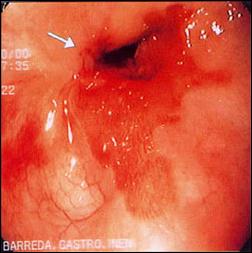

De la misma manera mostramos las características endoscópicas de la presentación del Esófago de Barrett sea corto o largo (Fig. 4). El Esófago corto de Barrett a su vez, tiene diversas variedades, siendo las más destacadas: la variedad en isla, la variedad en lengüeta o digitiforme y la variedad en unión escamo-columnar prominente(25,136). El Esófago largo de Barrett resalta de mejor manera cuando se utiliza material de tinción(115), nosotros destacamos, por contraste, el Esófago largo tubular al teñir con lugol el epitelio escamoso.

| Figura 4. Características endoscópicas en la presentación del Esófago de Barrett, secuencialmente desde la foto A hasta la G. |

Foto A. Esófago Corto de Barrett: Variedad en Isla.

Foto B. Esófago Corto de Barrett: Variedad en Isla.

Foto C. Esófago Corto de Barrett: Variedad en Lengüeta.

Foto D. Esófago Corto de Barrett: Variedad en Lengüeta.

Foto E. Esófago Corto de Barrett: Variedad UEC Prominente.

Foto F. Esófago Largo de Barrett

Foto G. Esófago Largo de Barrett: Tinción con Lugol.